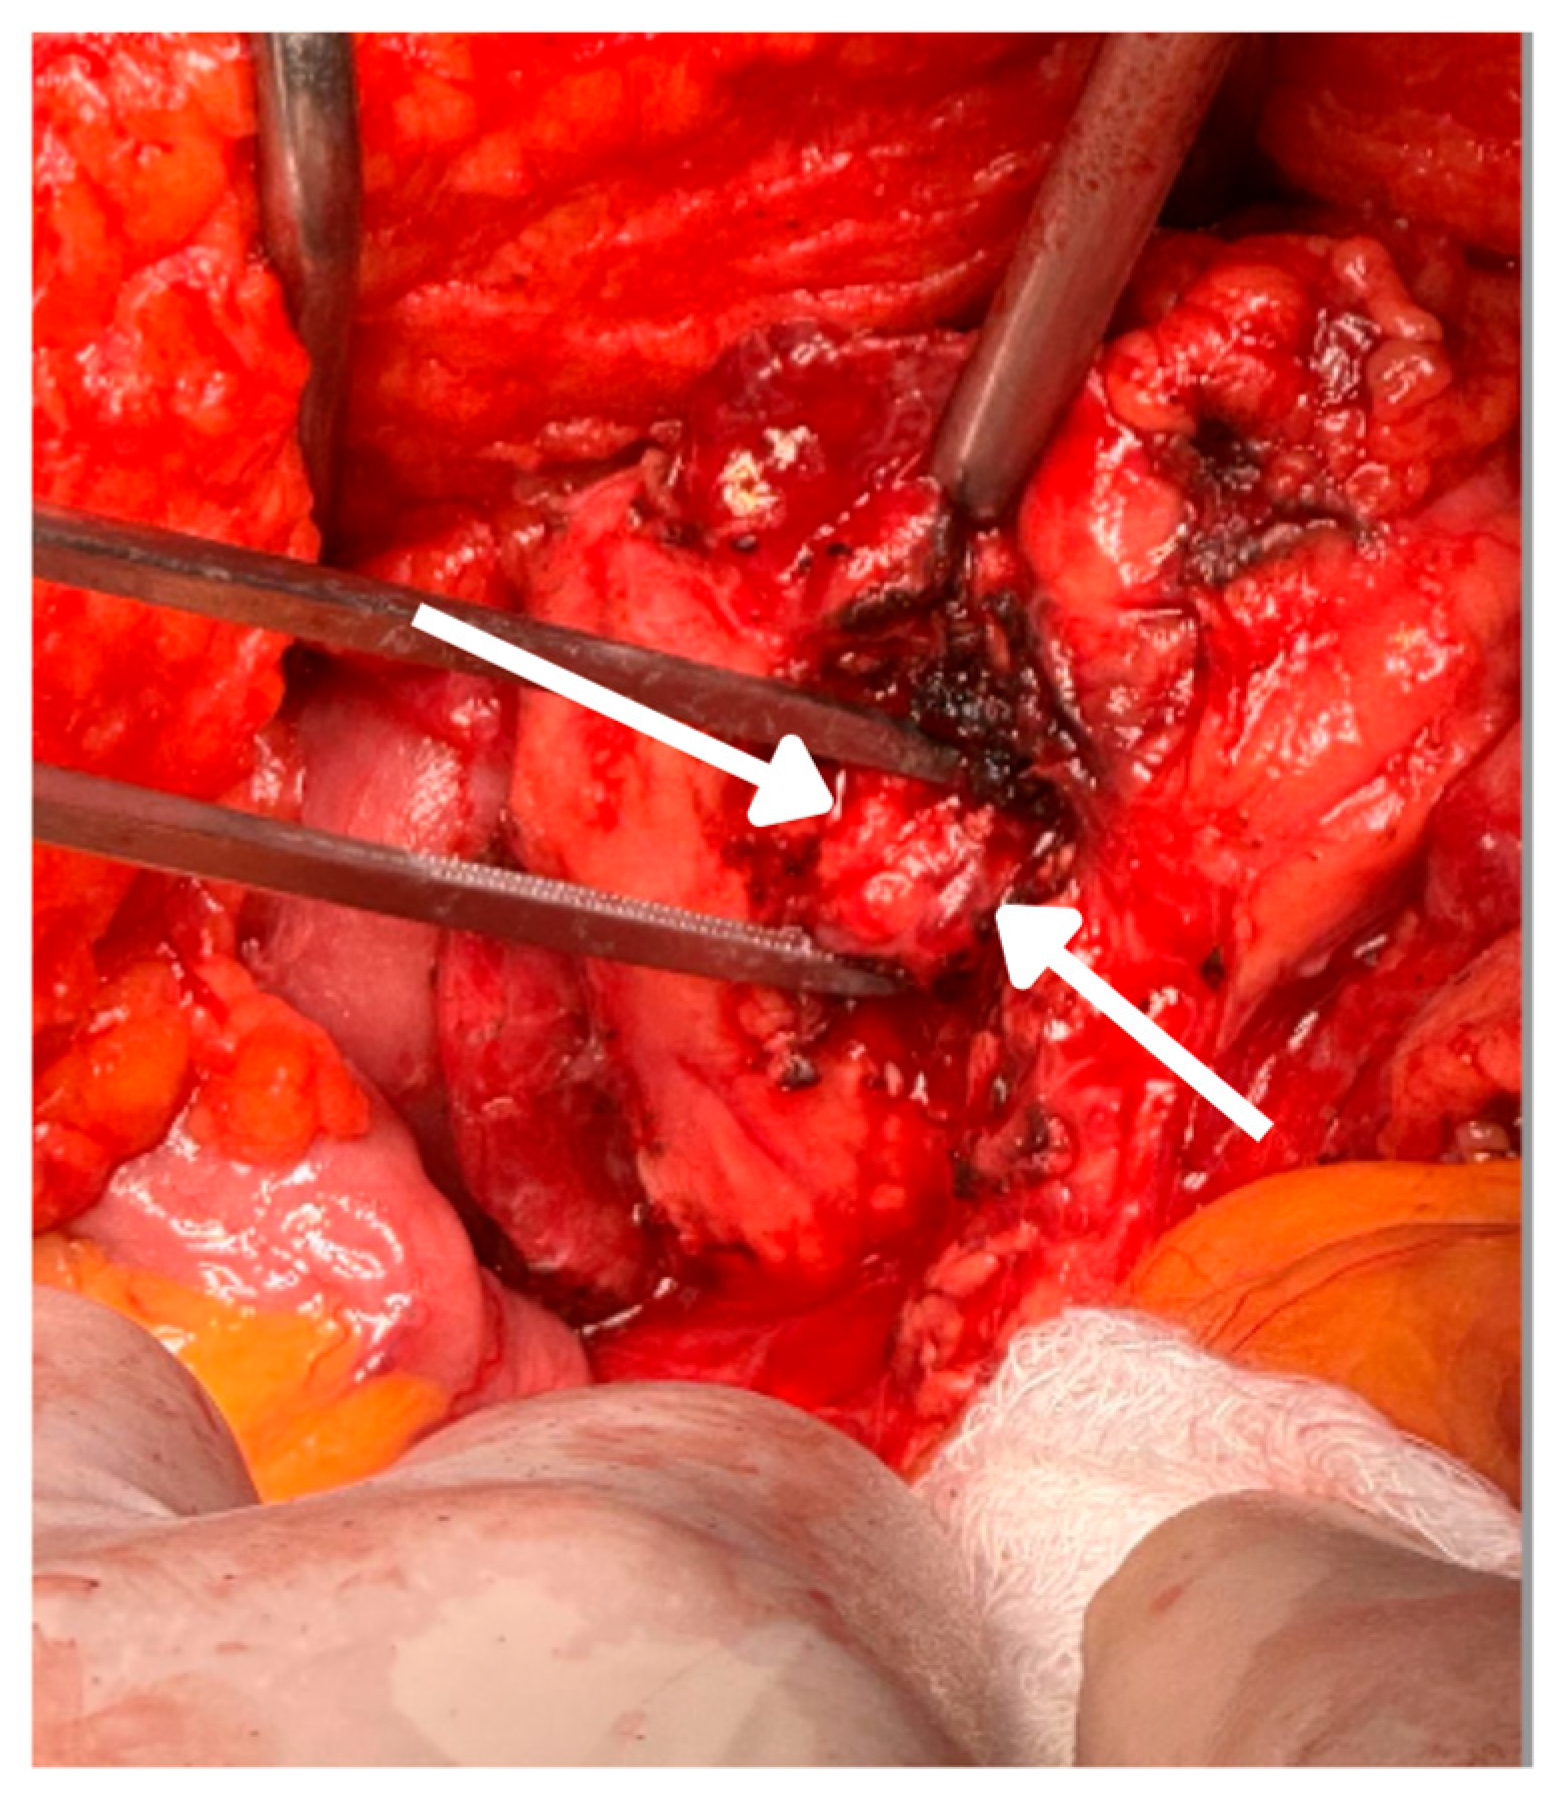

2.4. Surgical Intervention and Intraoperative Findings